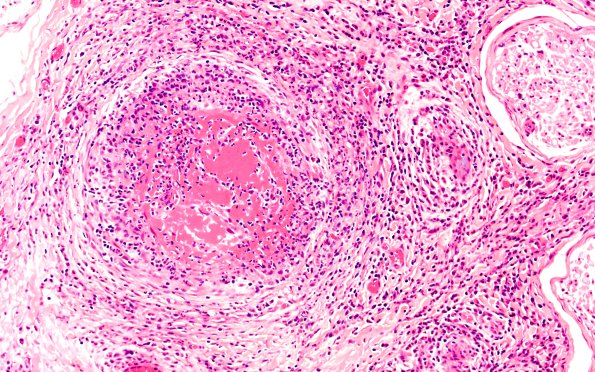

Washington University Experience | PERIPHERAL NEUROPATHY | 11 VASCULITIS - VASCULOPATHY | 4 Polyarteritis nodosa | 1A2 PAN (Case 1) H&E 20X 1

1A2,3 The structure of this arteriole is completely lost, replaced by a mixture of inflammatory cells including lymphocytes, PMNs and occasional plasma cells. Fibrin deposition is prominent. Hemorrhage is frequently seen accompanied by thrombosis. (H&E)